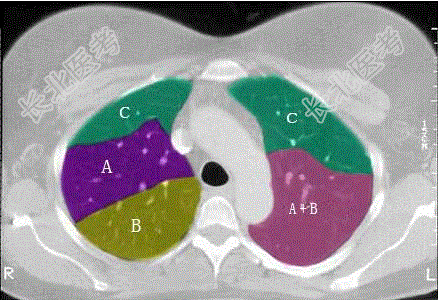

- 单项选择题结合肺段模式图,选出右肺下叶的组成

A、F

B、F+G

C、F+G+H

D、F+G+H+I

E、F+G+H+I+J